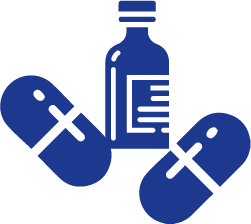

Cura comes with state-of-the-art world class facilities and is a multispecialty hospital situated in the heart of Kanakapura Road and Kammanahalli Bangalore. We at Cura are making the best of the exceptionally talented specialists and the latest equipment to provide you the best of medical facilities to ensure best health for you.

State-of-the-art technology and world-class expertise with the constant support of an extremely friendly administrative and supportive staff, the expert physicians who have degrees from abroad and best universities of India, we strive to give nothing short of best healthcare facilities. We have all kinds of latest technologies and well equipped Orthopedic surgery equipment in terms of recovery areas, operating theaters, and post therapy centers. Our operation theaters are well equipped with top class image intensifiers, top of the line arthroscopy system, computer navigation system, and operating microscope.